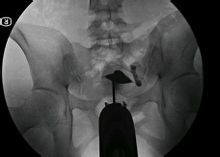

經X線片子閱讀

合格的造影是診斷的第一步,而明確的診斷卻是治療的關鍵,同一張片子不同的醫生由於經驗的不同會得出不同的結論,下面我們來看一些常見的片子。

1、正常的子宮輸卵管造影片子